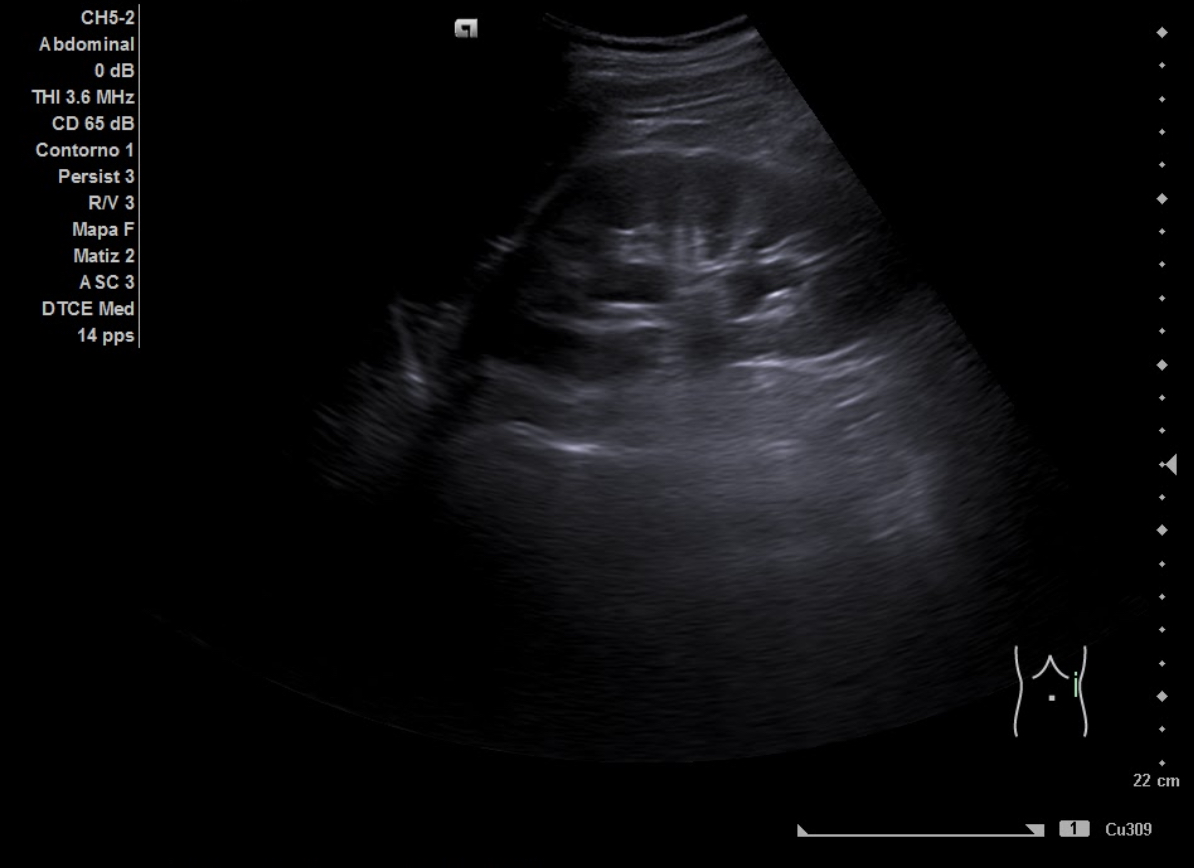

Ecografía aparato urinario en Centro de Salud: Riñones de tamaño normal, parénquima conservado con dilatación pielocalicial grado II-III izquierdo y grado II derecho. Vejiga con aspecto trabeculado, pared irregular con divertículos. Volumen premiccional 550 cc, postmiccional 450 cc. Volumen prostático de 50 cc.